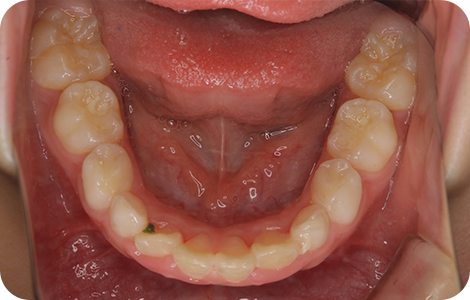

②子どもの矯正

BEFORE

AFTER

| 施術の説明 | 叢生を早期に改善する治療 |

|---|---|

| リスク・副作用 | 装置が入ることにより、虫歯のリスク、発音嚥下障害また一時的な顔貌の変化、正中の離開が起こります。 |

| 費用 | 462,000円 |

※税込表記です。